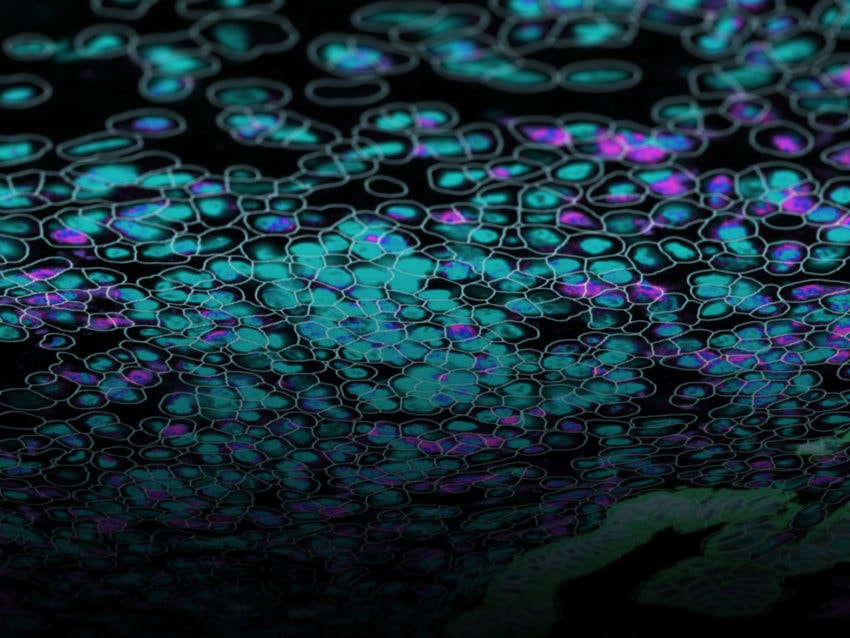

Preserving the cellular location of expressed RNAs within a tissue helps explain their biological role.

One technology accelerating the identification and use of biomarkers clinically is spatial transcriptomics (sometimes called spatial multiomics). Spatial transcriptomics surpasses previous next-generation sequencing techniques, such as single cell RNA seq, by framing tissue and cellular transcriptomic information in a spatial context, providing more precise analysis of the cellular biology and interactions involved in a given system. Characterization of gene expression spatial context is made possible by barcoded hybridization probes that identify transcripts while keeping the target tissue intact. Preserving the cellular location of expressed RNAs within a tissue helps explain their biological role. Additionally, spatial transcriptomics can be used to analyze protein expression for simultaneous characterization with RNA expression. The hybridization protocol used in spatial transcriptomics for screening barcoded probes removes cDNA library preparation or PCR amplification steps needed in single cell RNA seq that introduce potential errors.

NanoString has a complete spatial transcriptomics solution that includes CosMx SMI and an associated cloud based bioinformatics package, AtoMx® Spatial Informatics Platform (SIP). Using the CosMx SMI, users can use formalin-fixed paraffin embedded or fresh frozen samples to detect up to 1000 RNA and 64 protein samples at once. The multiomic output allows users to easily visualize cell boundaries and identify regions of interest (ROI). AtoMx SIP also will work with NanoString’s other spatial biology instrument, the GeoMx® Digital Spatial Profiler (DSP).